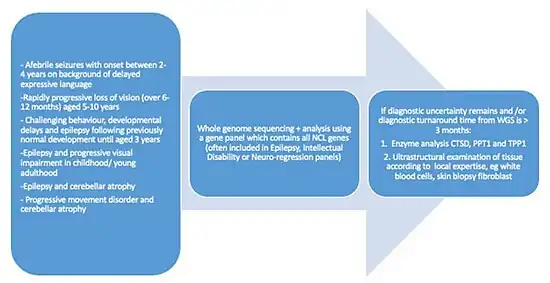

Diagnosis

Because vision loss is often an early sign, NCL may be first suspected during an eye exam. An eye doctor can detect a loss of cells within the eye that occurs in the three childhood forms of NCL. However, because such cell loss occurs in other eye diseases, the disorder cannot be diagnosed by this sign alone. Often, an eye specialist or other physician who suspects NCL may refer the child to a neurologist, a doctor who specializes in disease of the brain and nervous system. To diagnose NCL, the neurologist needs the patient's medical history and information from various laboratory tests.

Diagnostic tests used for NCLs include:

- Skin or tissue sampling: The doctor can examine a small piece of tissue under a microscope to spot typical NCL deposits. These deposits are found in many different tissues, including skin, muscle, conjunctiva, rectal and others. Blood can also be used. These deposits take on characteristic shapes, depending on the variant under which they are said to occur: granular osmophilic deposits (GRODs) are generally characteristic of INCL, while curvilinear profiles, fingerprint profiles, and mixed-type inclusions are typically found in LINCL, JNCL, and ANCL, respectively.

- Electroencephalogram or EEG: An EEG uses special patches placed on the scalp to record electrical currents inside the brain. This helps doctors see telltale patterns in the brain's electrical activity that suggest a patient has seizures.

- Electrical studies of the eyes: These tests, which include visual-evoked responses and electroretinograms, can detect various eye problems common in childhood NCLs.

- Brain scans: Imaging can help doctors look for changes in the brain's appearance. The most commonly used imaging technique is computed tomography (CT), which uses x-rays and a computer to create a sophisticated picture of the brain's tissues and structures. A CT scan may reveal brain areas that are decaying in NCL patients. An increasingly common tool is magnetic resonance imaging, which uses a combination of magnetic fields and radio waves, instead of radiation, to create a picture of the brain.

- Enzyme assay: A recent development in diagnosis of NCL is the use of enzyme assays that look for specific missing lysosomal enzymes for infantile and late infantile versions only. This is a quick and easy diagnostic test.

On April 27, 2017, the U.S. Food and Drug Administration approved cerliponase alfa (Brineura) as the first specific treatment for NCL. It is enzyme replacement therapy manufactured through recombinant DNA technology. The active ingredient in Brineura, cerliponase alfa, is intended to slow loss of walking ability in symptomatic pediatric patients 3 years of age and older with late infantile neuronal ceroid lipofuscinosis type 2 (CLN2), also known as TPP1 deficiency. Brineura is administered into the cerebrospinal fluid by infusion via a surgically implanted reservoir and catheter in the head (intraventricular access device).[23]

Enzyme replacement therapy

On April 27, 2017, the U.S. FDA approved cerliponase alfa as the first specific treatment for NCL.[23]